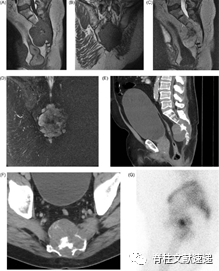

如患者出现神经功能障碍的症状或存在难以治疗的轴性疼痛时,应对其行MRI检查(如下图)。MRI可帮助其定位及定性,脊索瘤T1加权像呈低信号,T2加权像呈中高信号,并且可被造影剂轻中度增强。有研究表明,如在T2加权像上检测到的皮下脂肪浸润预示着预后较差。对于考虑手术治疗的患者,可常规行CT检查。CT结果常显示肿瘤呈溶骨性改变,并且病变常常起源于椎体,常侵犯骨皮质和周围软组织。

图注:累及S3-5的脊索瘤的影像学结果。可见病变累及骶骨并向骶前间隙侵犯。(A)矢状面和(B)冠状面MRI结果中T1加权像提示低信号改变,病变累及骶管。(C)矢状面和(D)冠状面T2压脂像提示累及骶神经根的高信号病变。(E)和(F)为增强CT结果显示病变累及骶骨。(G)为放射性示踪成像的结果